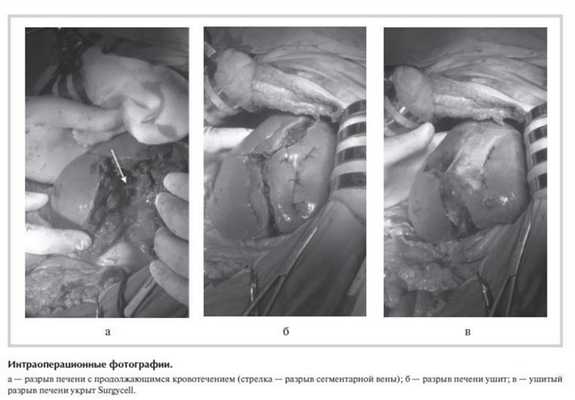

Через час после поступления больная оперирована. Под комбинированным интубационным наркозом с миорелаксацией сначала был вправлен вывих правого бедра. Затем произведена верхнесредне-срединная лапаротомия. В правом поддиафрагмальном пространстве, по правому латеральному каналу, в малом тазу около 900 мл крови. Обнаружен "звездчатый" разрыв S4-5-6

печени по диафрагмальной и висцеральной поверхности (наибольшая глубина разрыва 8 см) с интенсивным венозным кровотечением из него. Временный гемостаз тампонадой марлевыми салфетками, продолжена ревизия. Обнаружено небольшое правостороннее паранефральное кровоизлияние с пропитыванием. Других повреждений органов брюшной полости нет.

Разрез передней брюшной стенки расширен вправо с рассечением правой прямой мышцы живота, произведена коррекция доступа крючками Сигала. После удаления тампонов кровотечение возобновилось, в глубине разрыва обнаружены: 1) желчный проток S5 диаметром 3 мм с продольным разрывом длиной 4-5 мм и желчеистечением; 2) вена S5 диаметром 3 мм с разрывом овальной формы размером 4×2 мм (см. рисунок ). Выполнен прецизионный шов вены и желчного протока с использованием бинокулярной лупы с увеличением в 2,5 раза - соответственно восьмиобразным швом пролен USP 5/0 и непрерывным обвивным швом пролен USP 5/0 на атравматической игле.

Паренхиматозное кровотечение с поверхности печени остановлено электрокоагуляцией в биполярном режиме и "припудриванием" гемостатическим агентом Procol. С учетом перехода разрыва на висцеральную поверхность S4 печени близко от желчного пузыря выполнена холецистэктомия от шейки с раздельной перевязкой пузырного протока и артерии. Края разрыва печени сведены отдельными П-образными швами полигликолидом USP 0 на атравматической игле (см. рисунок б ), после чего линия швов укрыта гемостатическим агентом Surgycell (см. рисунок в ). Операция закончена дренированием брюшной полости и послойным ушиванием раны. Длительность операции 165 мин. Суммарная кровопотеря составила 1550 мл, собрано и реинфузировано аппаратом CellSaver 290 мл аутоэритроцитов.